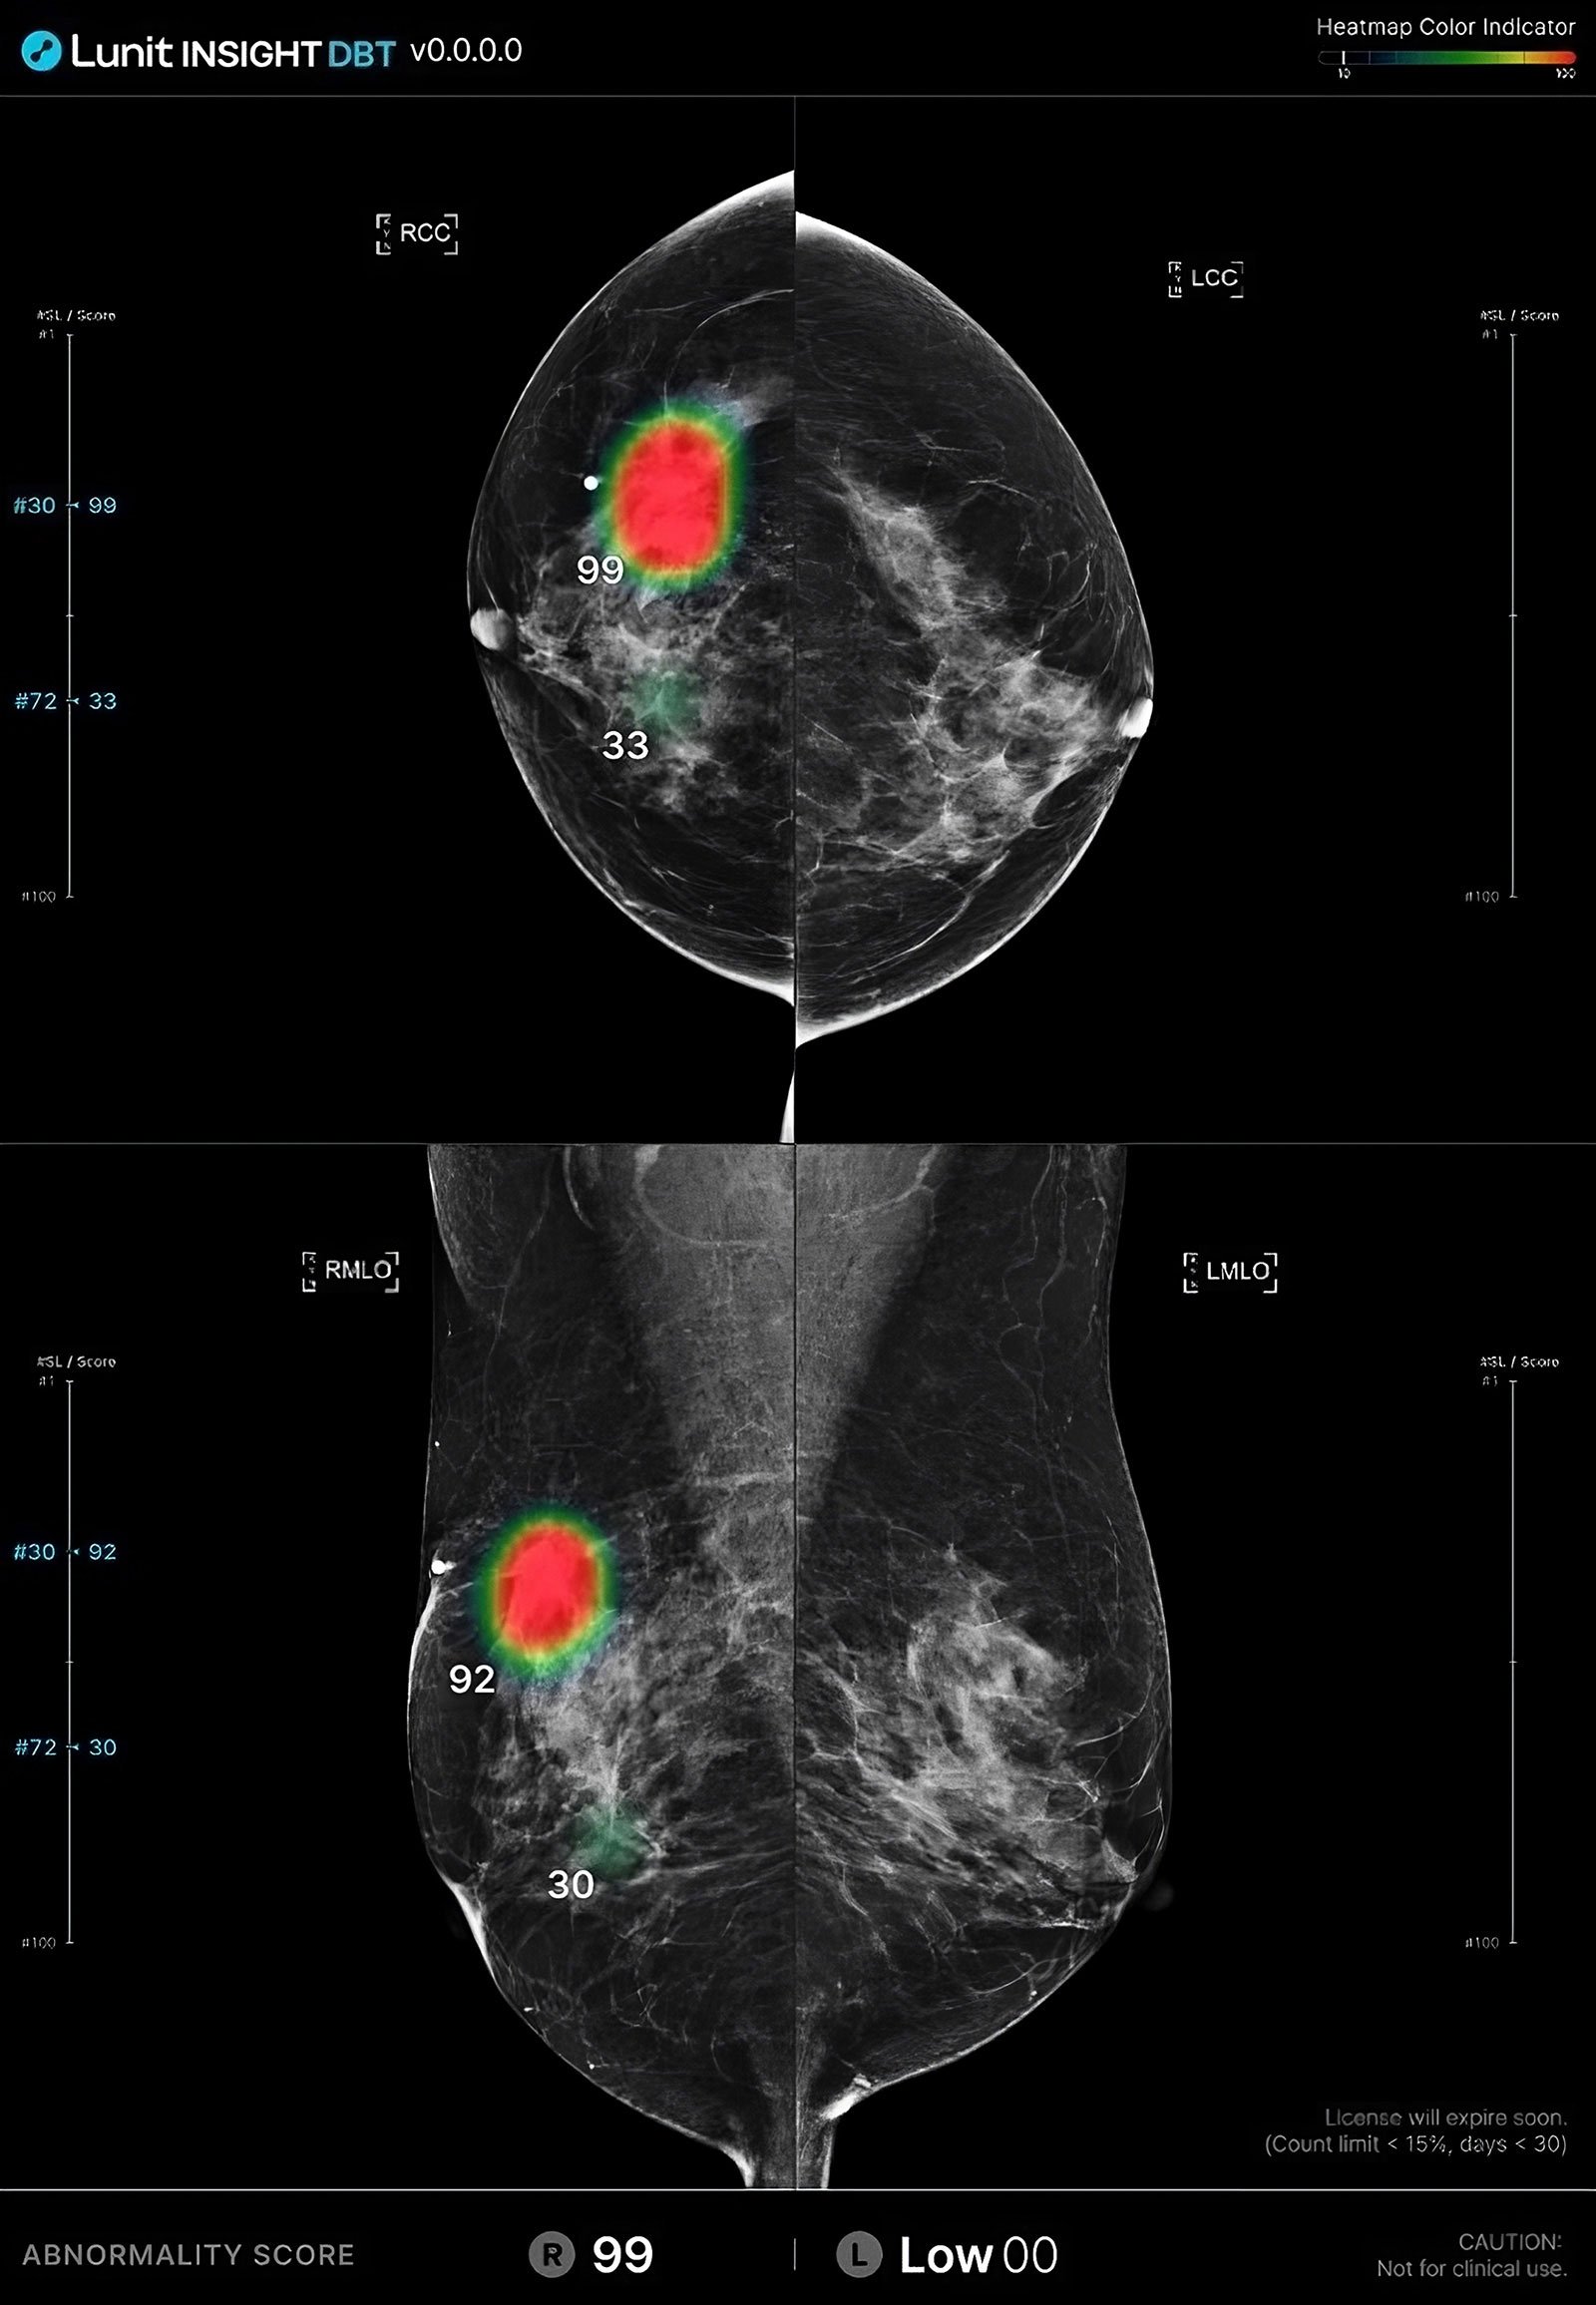

Akumin Selects Lunit INSIGHT DBT to Enhance Breast Imaging Services

AI-powered solution will improve workflow, accuracy, and confidence in breast cancer detection...